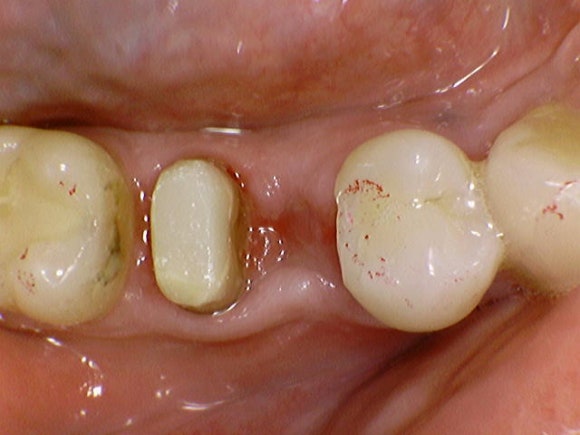

스페인에서 오신 60대 어르신이십니다.

요즘은 60대 분들의 활력이

젊은 세대 못지 않습니다.

정서적인 신체적인 건강 수준이

예전과는 많이 다릅니다.

그만큼 자연치아를 지키고자 하는 의지가

2030에 못지않게 강력하십니다.

어금니의 뿌리 한 쪽이 산산조각이

난 것을 보고는

일단 발치를 권해드렸습니다.

하지만 자연치아를 지키고자하는

환자분의 강력한 의지와,

제가 전공한 분야를 살리는 것

두 가지에 동기부여가 되어

치아절제술을 시도하였습니다.